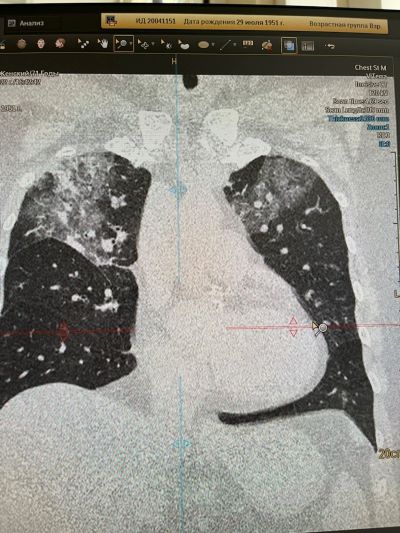

В клинике ВиТерра врачом-рентгенологом, КТ-диагностом было выполнено обследование на спиральном компьютерном томографе.

При исследовании были найдены значительные изменения в лёгочной ткани: на фоне "матового стекла" - выраженные участки консолидации, на фоне которых чётко определяются бронхоэктазы тракционные. Также определяются участки сотового лёгкого и объёмное уменьшение верхней доли справа.

Такие изменения на томограммах свидетельствуют об обычной интерстициальной пневмонии (идиопатический лёгочный фиброз).